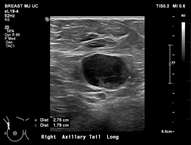

Ultrasound is the best modality for characterizing lymph nodes allowing for evaluation of shape, cortical thickness and presence or absence of fatty hilum. On ultrasound, normal axillary lymph nodes have an oval or lobulated shape with a preserved fatty hilum and cortical thickness less than 3 mm (figure 2). The echogenic hilum has arterial flow which can be assessed using color doppler imaging.

Features concerning for malignancy include round shape, increased cortical thickness and loss of fatty hilum1. The relationship of the lymph node cortex to hilum can be used to classify lymph node morphology and likelihood of malignancy. As the cortical thickness increases, there are reciprocal changes in the hilum beginning with hilar effacement and progressing to absence or replacement of the lymph node hilum2,3. Cortical thickening (figure 3) is considered the earliest morphologic change associated with malignancy; however, this finding is nonspecific with a low positive predictive value1-3. Absent/replaced hilum (figure 4) is the most specific for malignancy with a positive predictive value of 58-97%2.